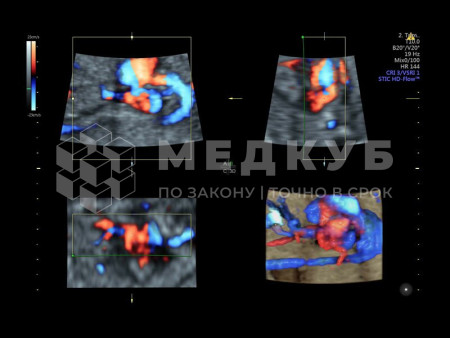

— Технология HDlive Flow значительно улучшает качество изображения сосудистых систем, обеспечивая более четкое восприятие их глубины в сравнении с классической цветовой допплерографией и HD-Flow. При этом, современный метод объемной томографии с улучшенным контрастом (Volume Contrast Imaging, VCI) в сочетании с функцией OmniView значительно усиливает контрастное разрешение, повышая качество изображений интересующих областей в различных плоскостях среза, что особенно важно при работе со структурами сложной формы. - Функция SonoRenderlive значительно улучшает качество трехмерной визуализации, автоматически адаптируя позицию линии реконструкции для более точного воспроизведения поверхностных структур. В четырехмерном режиме эта технология обеспечивает динамическое обновление базовой линии в соответствии с движениями развивающегося плода. Ультразвуковой аппарат Voluson E10 выделяется высокой производительностью и простотой в использовании. Его инструменты разработаны таким образом, чтобы максимально сократить время, затрачиваемое на работу с системой.